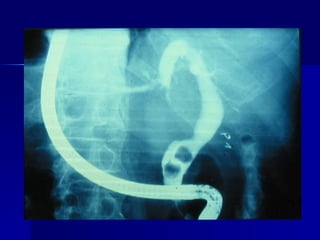

Ictericia datos paraclínicos: COLANGIO PANCREATOGRAFIA  RETROGRADA ENDOSCOPICA  (CPRE) MÁS ÚTIL CON CANALES NO DILATADOS  REVELA MEJOR LOS CONDUCTOS EXTRAHEPATICOS DIAGNÓSTICO Y TERAPIA DE PATOLOGIA PAPILAR (VATER) PERMITE EXTRAER CÁLCULOS COLOCA CATETERES

Ictericia datos paraclínicos:COLANGIO PANCREATOGRAFIA RETROGRADA ENDOSCOPICA (CPRE) MÁS ÚTIL CON CANALES NO DILATADOS REVELA MEJOR LOS CONDUCTOS EXTRAHEPATICOS DIAGNÓSTICO Y TERAPIA DE PATOLOGIA PAPILAR (VATER) PERMITE EXTRAER CÁLCULOS COLOCA CATETERES